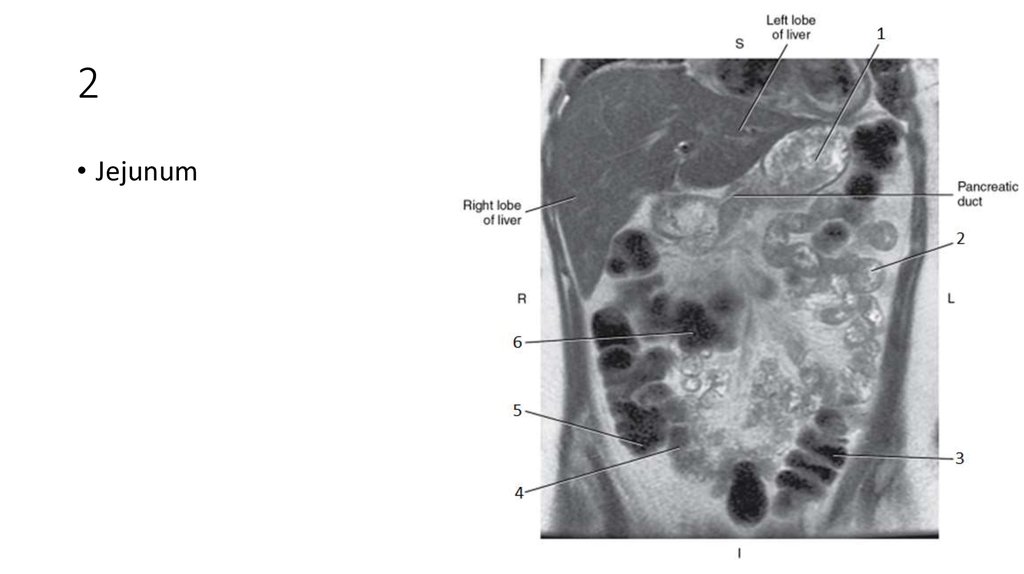

50. 1

51. 1

• Stomach

52. 2

53. 2

• Jejunum

54. 3

55. 3

• Descending Colon

56. 4

57. 4

• Ileum

58. 5

59. 5

• Cecum

60. 6

61. 6

• Transverse Colon